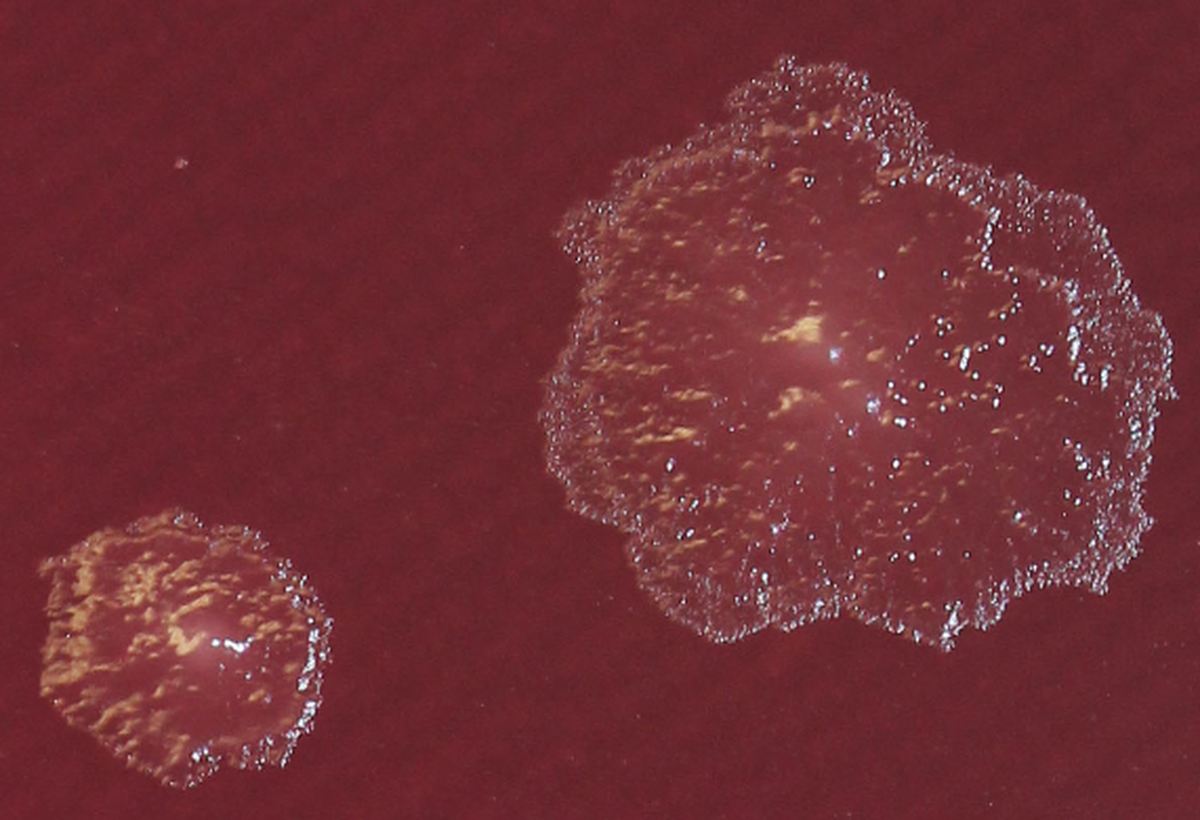

Колония Turicibacter sp. H121